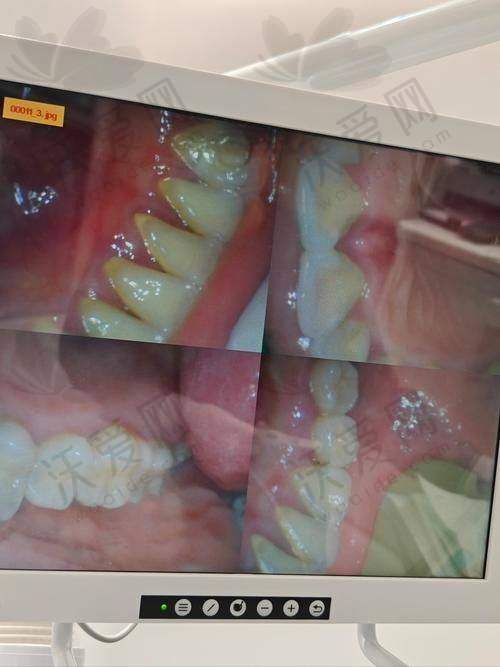

长春传阳口腔在洗牙项目上采用了精良的超声波洗牙技术。这种技术通过超声波的高频震动,能够有效地去除牙齿表面的牙结石、牙菌斑和色素沉着。与传统的洗牙方法相比,超声波洗牙具有以下优势:

效率高清洁:超声波的高频震动可以快速击碎牙结石和牙菌斑,清洁成效显著。能够深入到牙齿的各个角落,包括牙缝、牙龈沟等难以清洁的部位,确保牙齿得到全方面的清洁。

保持口腔卫生:洗牙是一种有效的口腔清洁方法,可以去除日常刷牙难以清除的污垢,保持口腔清洁。每天刷牙只能清洁牙齿表面的部分污垢,而洗牙可以深入清洁牙齿,预防口臭、龋齿等问题。

改善牙齿外观:长期吸烟、喝咖啡、喝茶等习惯会导致牙齿表面色素沉着,使牙齿变黄变黑。洗牙可以去除这些色素,修复牙齿的洁白色泽,让你的笑容更加灿烂。

预防口腔疾病:牙结石和牙菌斑是导致口腔疾病的主要原因。洗牙可以及时去除这些有害物质,预防牙龈炎、牙周炎等疾病的发生。同时,洗牙还可以发现早期的口腔问题,如龋齿、牙龈萎缩等,及时进行治疗。